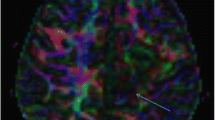

Color-coded FA maps representing the primary direction of water diffusion with the convention that blue represents water diffusion in the superior to inferior or inferior to superior direction, red represents left to right or right to left diffusion, and green represents anterior to posterior or posterior to anterior diffusion.

Tractography images that provide information on the coherence of water diffusion over many voxels through reconstruction of “tracts.” If the same color coding as in the FA maps is used, blue fibers represent primarily projection fibers, red fibers represent primarily interhemispheric connections and fibers, and green fibers represent interhemispheric connections.